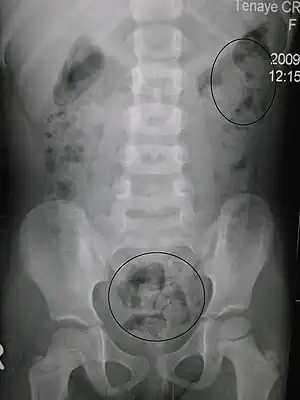

Obstipação ou constipação intestinal, popularmente denominada prisão de ventre, é uma condição caracterizada por defecações pouco frequentes ou de difícil passagem.[1] As fezes apresentam-se geralmente duras e secas.[2] Entre outros sintomas estão dores abdominais, sensação de ventre inchado e uma sensação semelhante a não ter defecado por completo.[3] As complicações mais comuns das obstipações são hemorroidas, fissura anal ou acumulação de fezes no intestino grosso.[2] A frequência normal de defecações em adultos é entre três por dia e três por semana.[2] Os bebés geralmente realizam três a quatro defecações por dia e as crianças duas a três.[4]